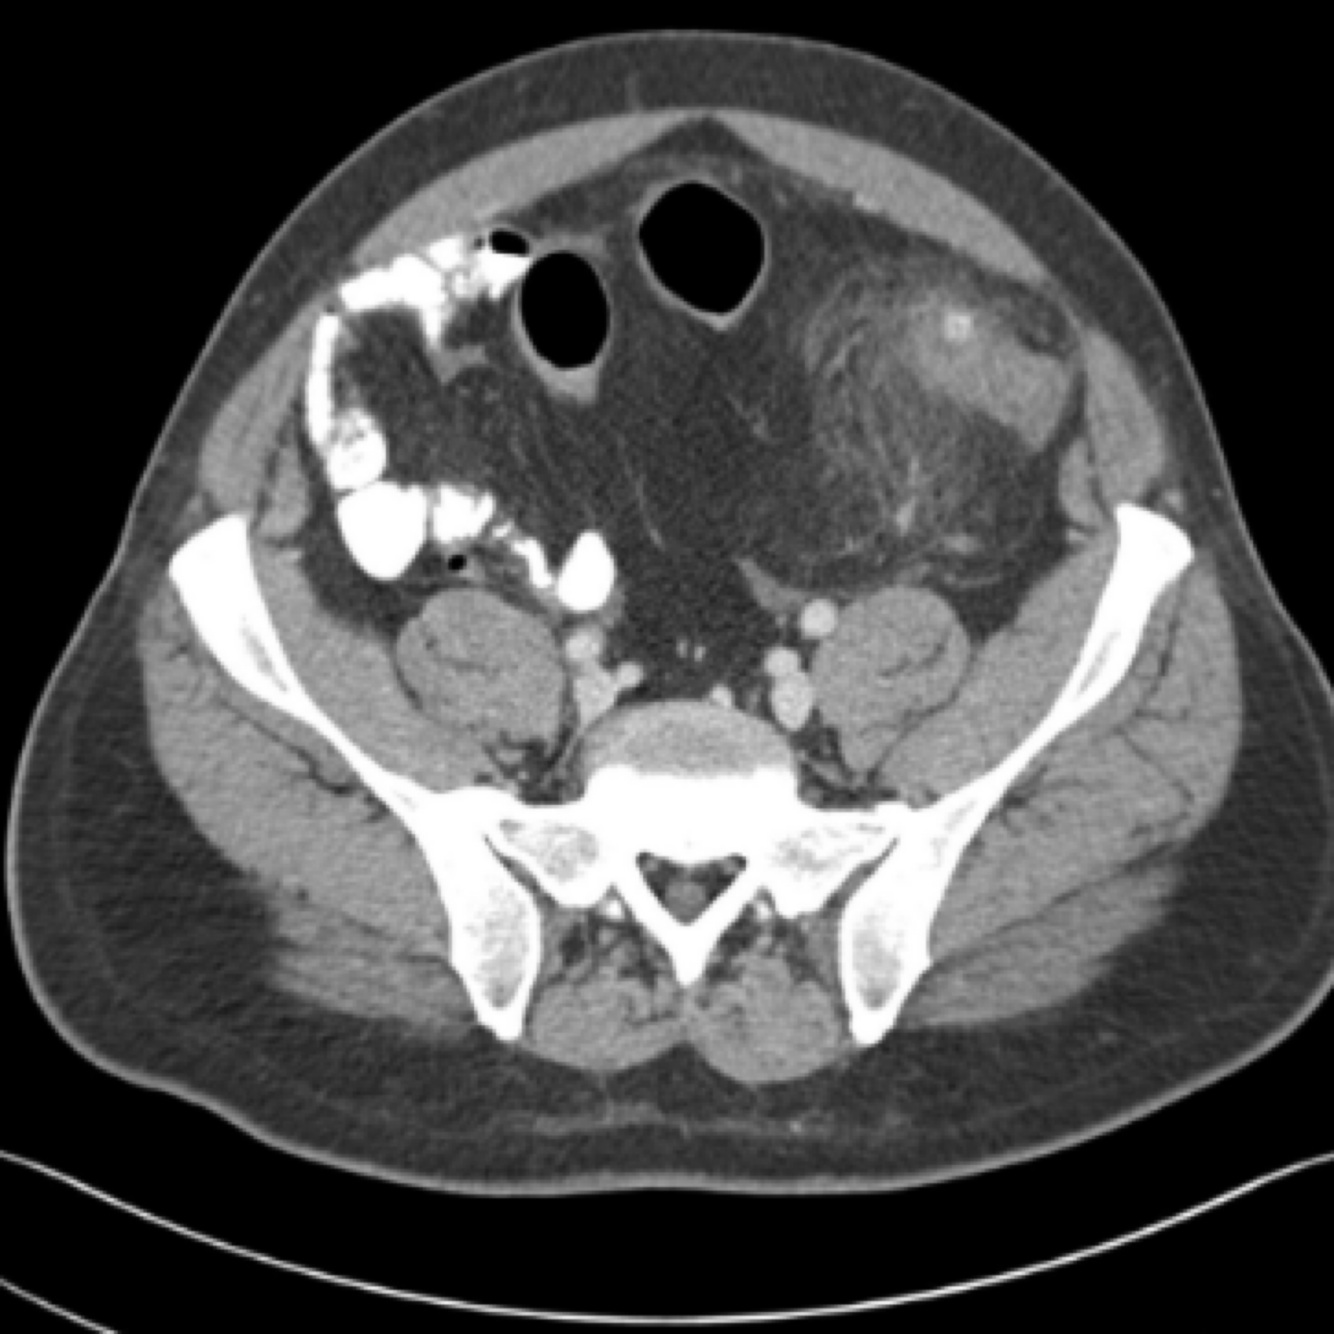

diverticulitis